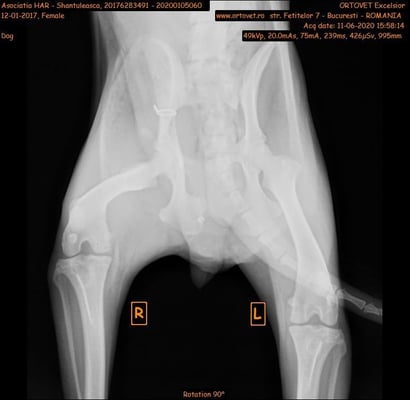

Shanya wurde von einem Auto angefahren und lag dann zwei Tage verletzt im Straßengraben, ehe sich jemand erbarmt hat und Grig um Hilfe bat.

Sie wird voraussichtlich zwei Operationen brauchen, eine davon am Becken, die sehr kompliziert ist. Die Kosten hierfür liegen bei 1500,- Lei = 300,- Euro. Wenn das alles gut überstanden ist, wird sie wahrscheinlich irgendwann eine weitere OP benötigen, um die Metallimplantate wieder zu entfernen. All das kostet leider eine Menge Geld.

Shanya was hit by a car and then lay injured in a ditch for two days before someone showed mercy and asked Grig for help.

She will probably need two surgeries, one of them on the pelvis, which is very complicated. The costs for this are 1500,- Lei = 300,- Euro. If all this is well done, she will probably need another surgery sometime to remove the metal implants again. All this unfortunately costs a lot of money.